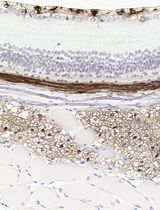

Improved Immunohistochemistry of Mouse Eye Sections Using Davidson's Fixative and Melanin Bleaching

Anne Nathalie Longakit [...] Catherine D. Van Raamsdonk

Nov 20, 2025 1562 Views